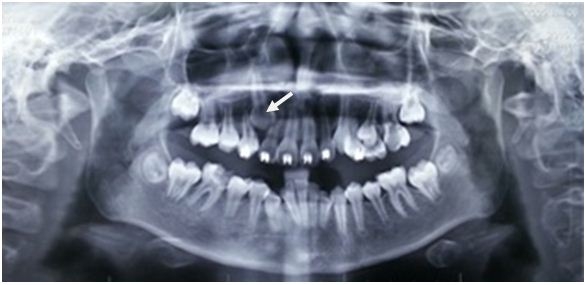

Xử trí răng mọc ngầm

TheoTS.BS.Nguyễn Phú Thắng : Răng ngầm là một hay nhiều răng nằm trong xương hàm trên hay xương...

Cấy chuyển răng – kỹ thuật cao

Tại Việt Nam , Từ năm 2012 , TS.BSNT.Nguyễn Phú Thắng và học trò cũng áp dụng phương...